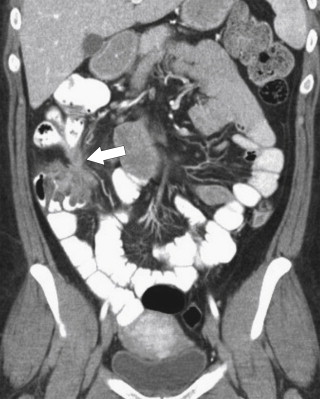

Other differentiating features of UC include a propensity for Crohn disease to fistulize with the small bowel, with adjacent organs, or to the skin. This can be assessed by CT ( Fig. 5-23 ), BE ( Figs. 5-24 and 5-25 ), or MRI ( Fig. 5-26 ). Abscess formation is also recognized in Crohn disease rather than UC ( Fig. 5-27 ). An increased risk of small and large bowel malignancies, predominantly adenocarcinomas, is associated with Crohn disease ( Fig. 5-28 ).

Figure 5-23, Coronal CT in a 38-year-old woman with a coloenteric fistula ( arrow ) due to Crohn disease.